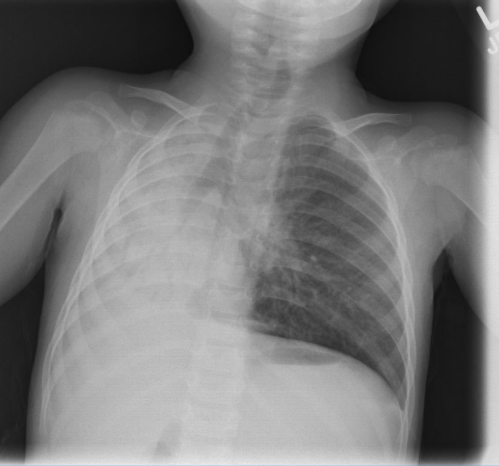

Nine months later, recurrent wheezing prompted a referral to pulmonary specialists. A follow-up chest X-ray three months after the initial infection showed alarming changes: complete opacification of the right hemithorax, a mediastinal shift to the right, and collapse of the right upper and middle lobes.

A follow-up chest X-ray fifteen months after her initial presentation continues to show hyperlucency of the left lung. This case underscores the importance of recognizing SJMS as a potential complication of early childhood respiratory infections, allowing for timely intervention to mitigate long-term lung damage.